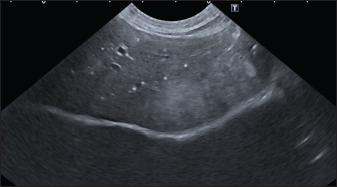

In the branched pattern, mineralizations were usually sub-centimetric or centimetric and they replicated the shape of the intrahepatic biliary tree (Fig. 3). Also in this case, sub-centimetric and centimetric IBTM determined a focal dilatation of the biliary ducts observed in 65.6% of dogs (21/32) (Fig. 4). In six of them (18.7%), we found millimetric IBTM randomly distributed in the liver.

Fig. 3. Ultrasound image of the liver showing sub-centimetric and centimetric IBM, generating acoustic shadow, with a branched pattern.